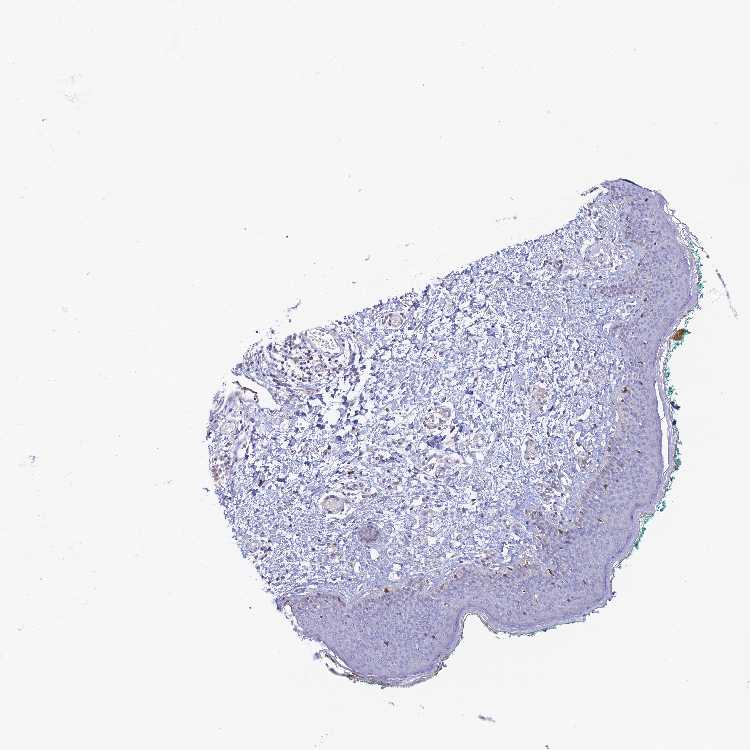

SKIN 1 - Antibody stainingi

Antibody staining in the annotated cell types in the current human tissue is reported as not detected, low, medium, or high, based on conventional immunohistochemistry profiling in selected tissues. This score is based on the combination of the staining intensity and fraction of stained cells.

Each image is clickable and will lead to virtual microscopy that enables deeper exploration of all samples and also displays staining intensity scores, fraction scores and subcellular localization as well as patient and tissue information for each sample.

Antibody HPA042981

Langerhans Medium

Fibroblasts Low

Keratinocytes Low

Melanocytes Medium